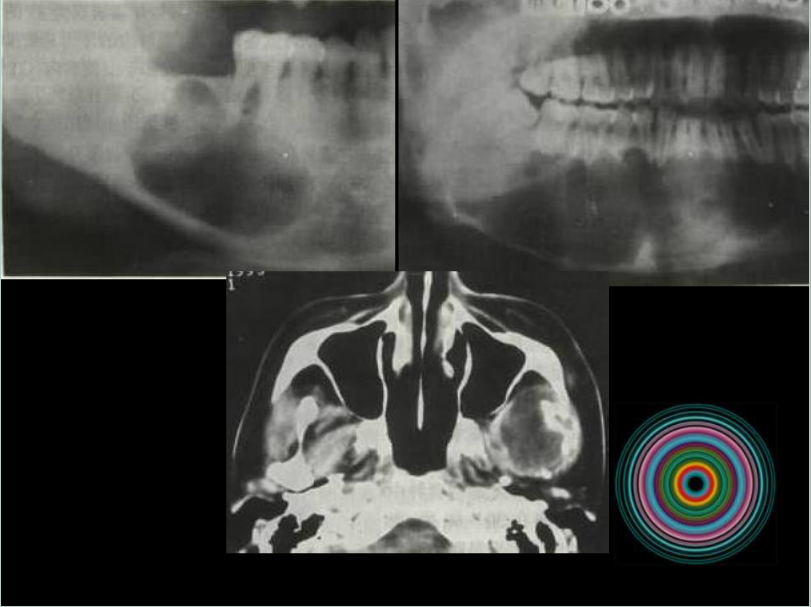

口腔頜面外科 影像技術(shù)